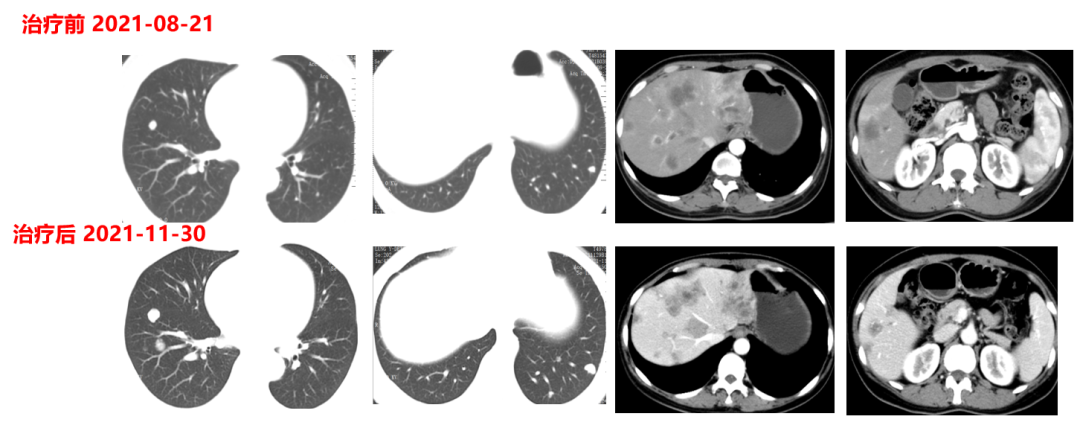

一线治疗(2021-4-17至2021-11-30,PFS:6月余):

于2021.04.17行“FOLFOX6”方案化疗1周期,行“奥沙利铂”化疗时,出现严重过敏。因患者基因状态为RAS,BRAF野生型,第2周期始给予“FOLFIRI+西妥昔单抗”,在治疗过程中,肿瘤标志物持续下降,影像学也显示肝脏病灶明显缩小。疗效评价PR,在2021-09-25在局麻DSA下行“肝动脉造影并化疗灌注栓塞术”。

肿瘤初次进展(2021-11-30)

患者于2021年11月30号复查时,肺上病灶增大增多,肝脏病灶稍增大,肿瘤标志物增高,整体疗效评价PD,考虑一线治疗进展。